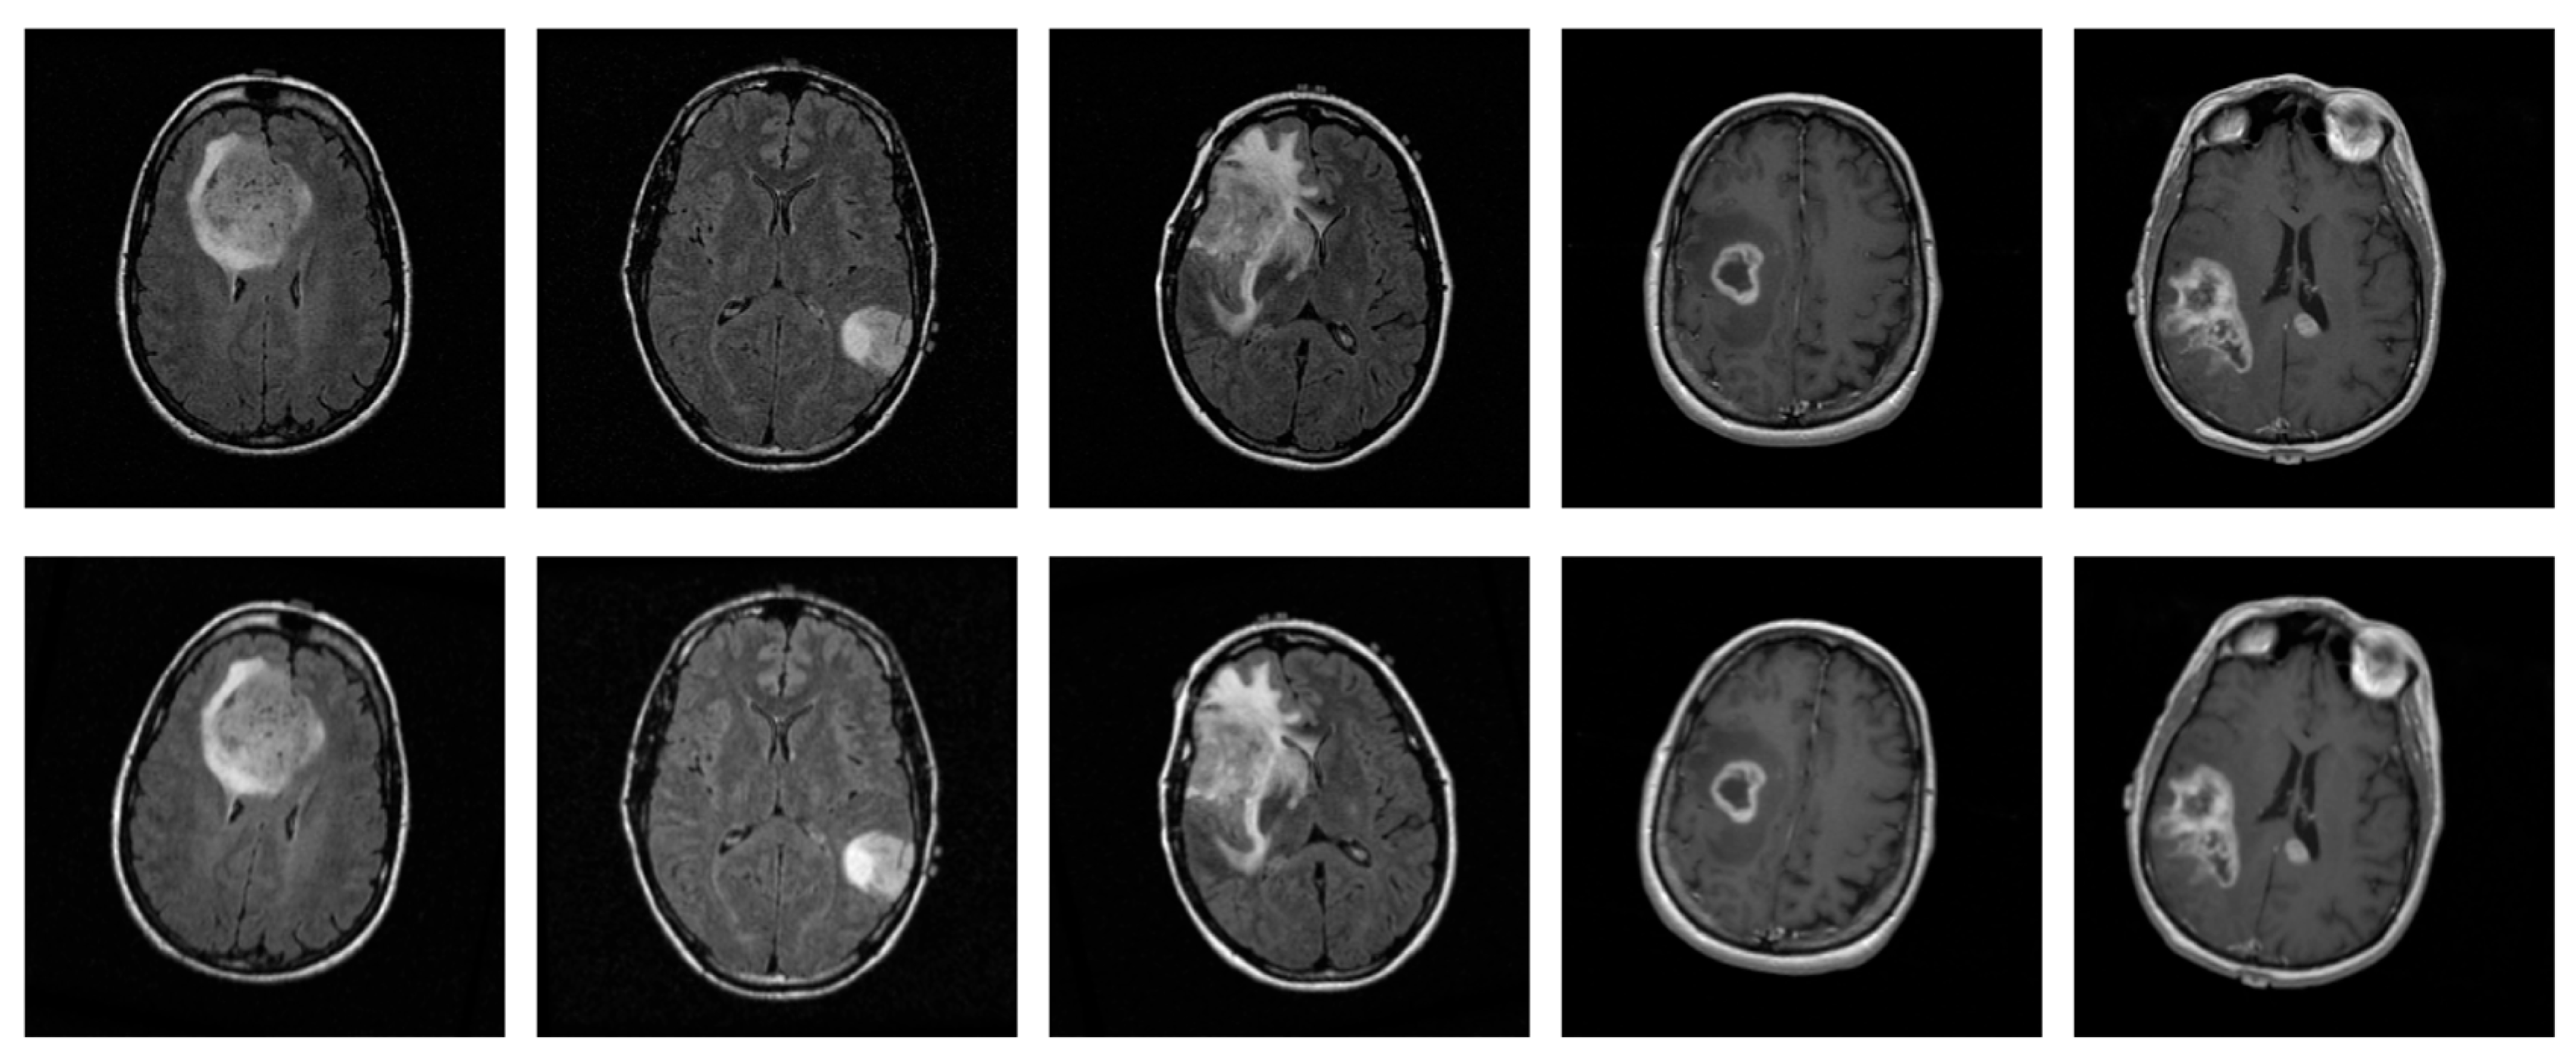

The selected data originate from various MRI scanners manufactured by Siemens and GE, with slice thickness ranging from 2.5 to 5.0 mm, thereby providing variability and removing scanner-related bias limitation in the proposed method. A representative sample of each grade is presented in Figure 1.

Figure 1. Representative 2D MRI slices of astrocytomas from each grade in the dataset: Grade 2 (left), Grade 3 (center), and Grade 4 (right).